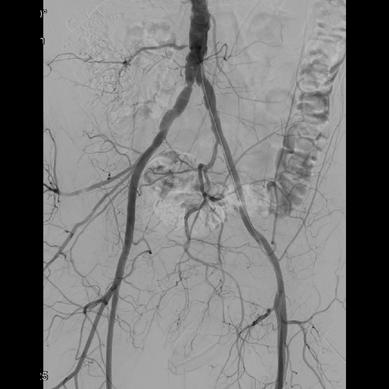

The focus of their study was to establish the role of IR in the management of potentially lifethreatening postpancreatectomy complications such as PPH, thus preventing re-exploration. To do so, Kulkarni and colleagues enrolled 758 patients who underwent pancreatic surgery between January 2014 and December 2019. All patients who developed post-surgical complications within 90 days of primary hospitalisation were included. Complications were classified according to the International Study Group of Pancreatic Surgery (ISGPS).

The types of surgery included in the study were pancreatectomy (4%), pancreaticoduodenectomy (73.8%), enucleation (1%), pancreatectomy and vein resection (4.85%), and multivisceral pancreatic surgery (16.5%). Of the 758 patients included, 206 (27.2%) developed post-surgical complications. Of these, 46 patients (6%) experienced PPH, with 30 patients (3.96%) requiring intervention; 13 patients (43.3%) underwent angioembolization, of whom five (38.46%) died due to causes unrelated to PPH, while 17 patients (56.7%) underwent surgical reexploration.

The authors note that the 90-day mortality rate in patients with PPH was 17.39%, which is comparable

with other studies in the literature. For patients who underwent primary angioembolization for PPH, the mortality rate was 38.46%—which is not statistically significant, they detail. The causes of death for these five patients included biliary sepsis with multiorgan dysfunction, myocardial infarction, hepatic decompensation, and major hepaticojejunostomy and pancreatojejunostomy leaks. Kulkarni and colleagues state that “although PPH may have been a contributing factor, the causes of death were not directly related to the condition”.

“These five patients who underwent re-exploration were beyond the scope of management by IR,” state Kulkarni and colleagues, who explain that mortality rates in patients with PPH “remain high despite aggressive intervention”. They do note, however, that these patients also tend to have associated complications and comorbidities which contribute to increased mortality and morbidity rates. They describe that common comorbidities among this patient population are diabetes, hypertension, hypothyroidism and coronary artery disease; 45 patients in their study cohort presented with one comorbidity and 47 with multiple.

Elsewhere in their results, the researchers observed intra-abdominal fluid collections in 173 (22.8%) patients, with 147 (85%) undergoing image-guided interventions and 23 (13.3%) undergoing surgical re-exploration. The 90-day mortality rate after percutaneous image-guided intervention was 6.12% and after primary surgical re-exploration was 21.7%.

Among other results, the authors identified that biliary complications occurred in 31 patients (4%), of which 18 (58%) underwent image-guided intervention and 11 (35.5%) underwent surgical re-exploration. The 90-day mortality rates were 27.78% and 35.5% in the IR and surgical groups, respectively. Further,

the incidence of pancreatic fistula was observed in 20% of patients, 91.8% of whom were prevented from undergoing surgical re-exploration by use of IR management. The 90-day mortality rate in patients who underwent percutaneous drainage was 2.7% and 30.3% in those who underwent primary surgical re-exploration.

“Image-guided interventions successfully prevented re-exploration in 61.5% of PPH cases, 88.9% of biliary complications, and 99.3% of intra-abdominal fluid collections,” state Kulkarni et al, emphasising the “pivotal role” IR plays in managing post-surgical complications.

“IR provides a minimally invasive alternative to surgical re-exploration, reducing recovery time and preventing morbidity associated with re-exploration,” say the authors. They highlight that “early recognition and prompt intervention” are key in patients with PPH, biliary leak and portal vein thrombosis, as these are conditions associated with high mortality and morbidity rates. However, in cases where surgical re-exploration is required, this is “often due to complications which are beyond the scope of percutaneous management”, Kulkarni et al point out.